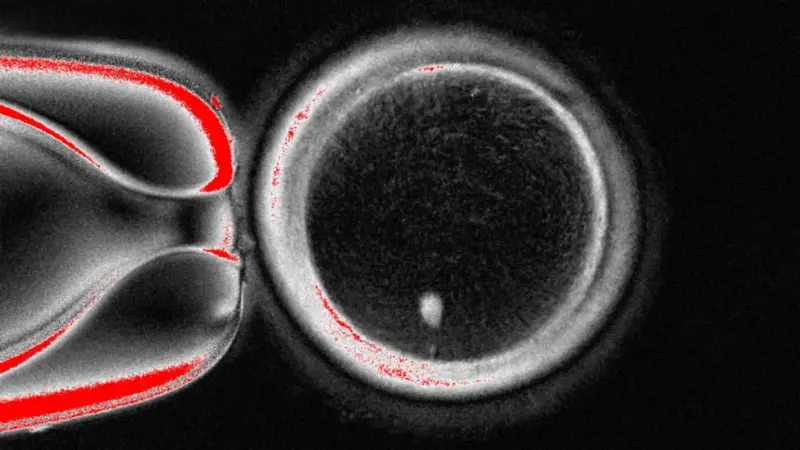

Investigadores de la Universidad de Salud y Ciencias de Oregón (Estados Unidos) lograron por primera vez crear embriones humanos en...